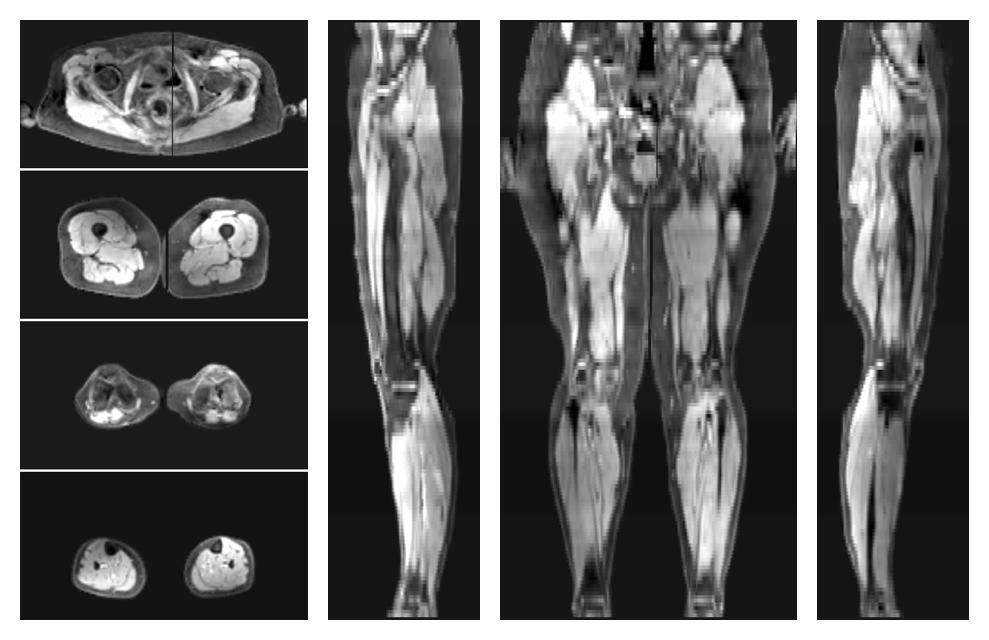

• Water only signal

The water part of the acquired multi-echo spin echo data.

• Water only T2 relaxation time

The water only T2 relaxation time of the lower extremity obtained from multi echo spin echo t2 mapping with EPG based reconstruction.